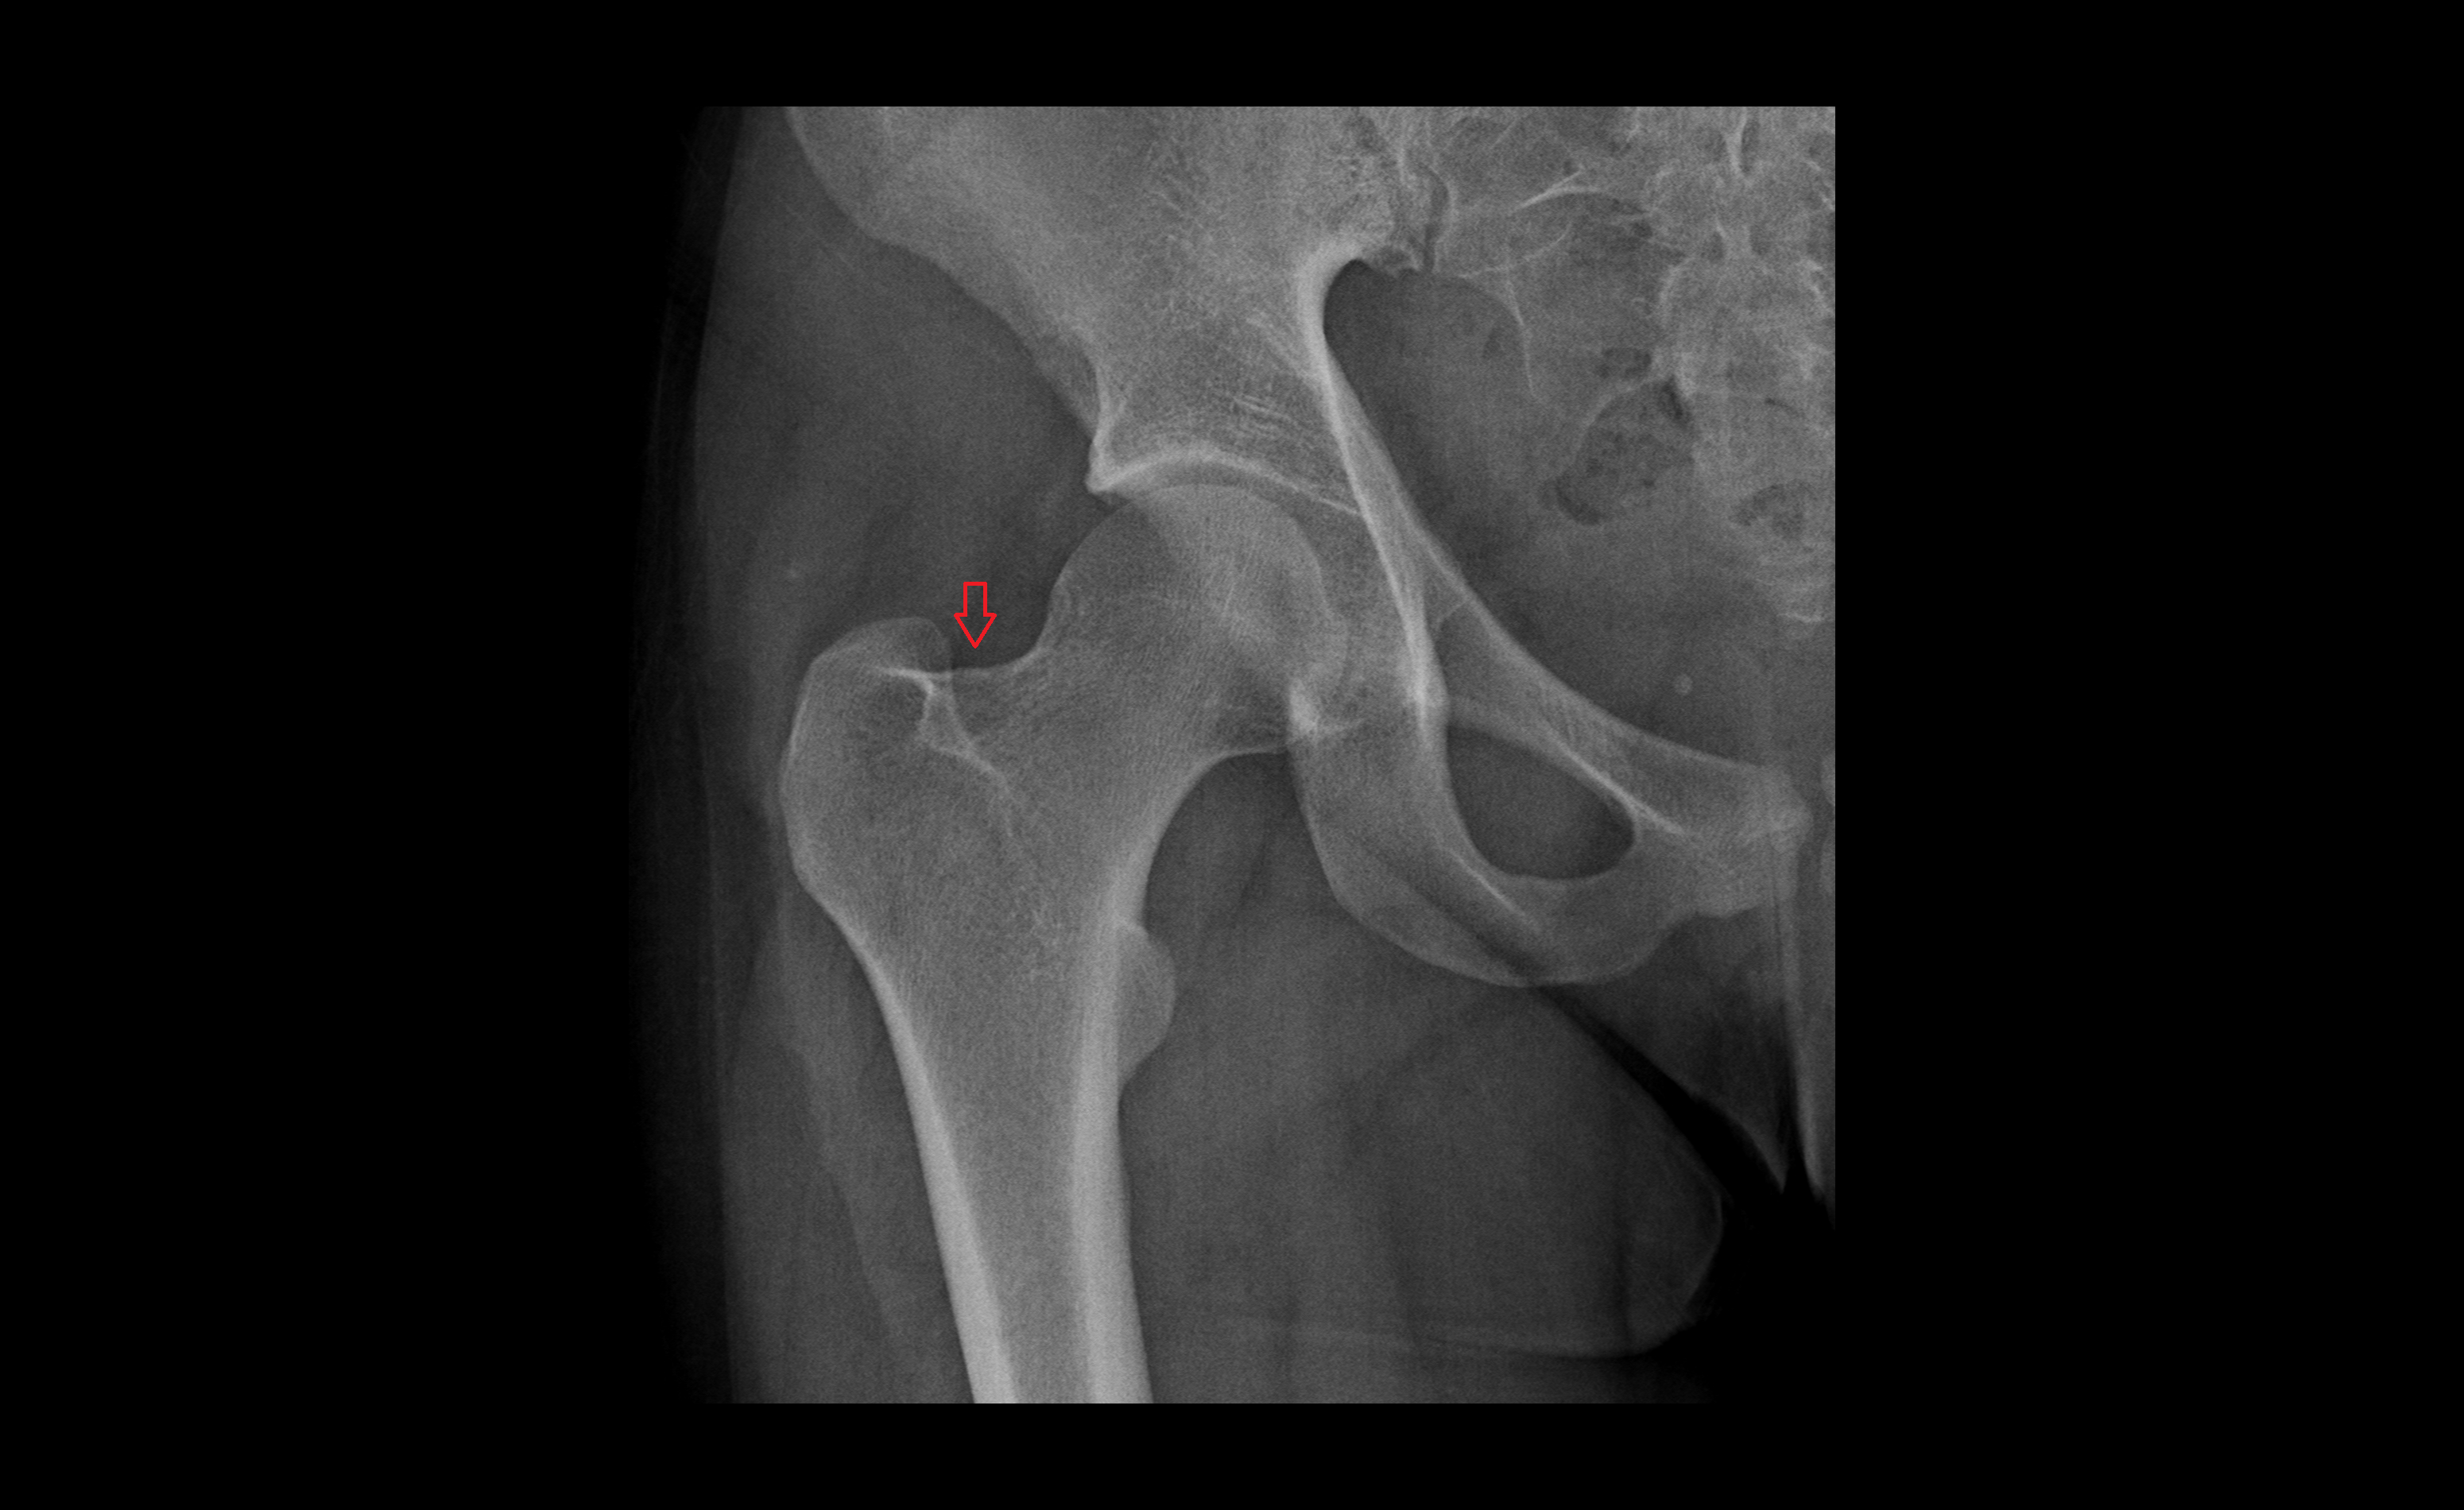

- Head of femur

- Neck of femur

- Acetabulum

- Hip joint